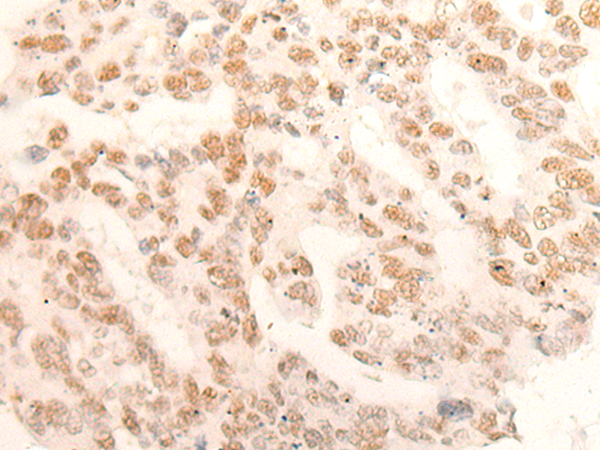

分类: 科研抗体货号: P13188别名: GES; GD:REM应用: IHC反应种属: Human